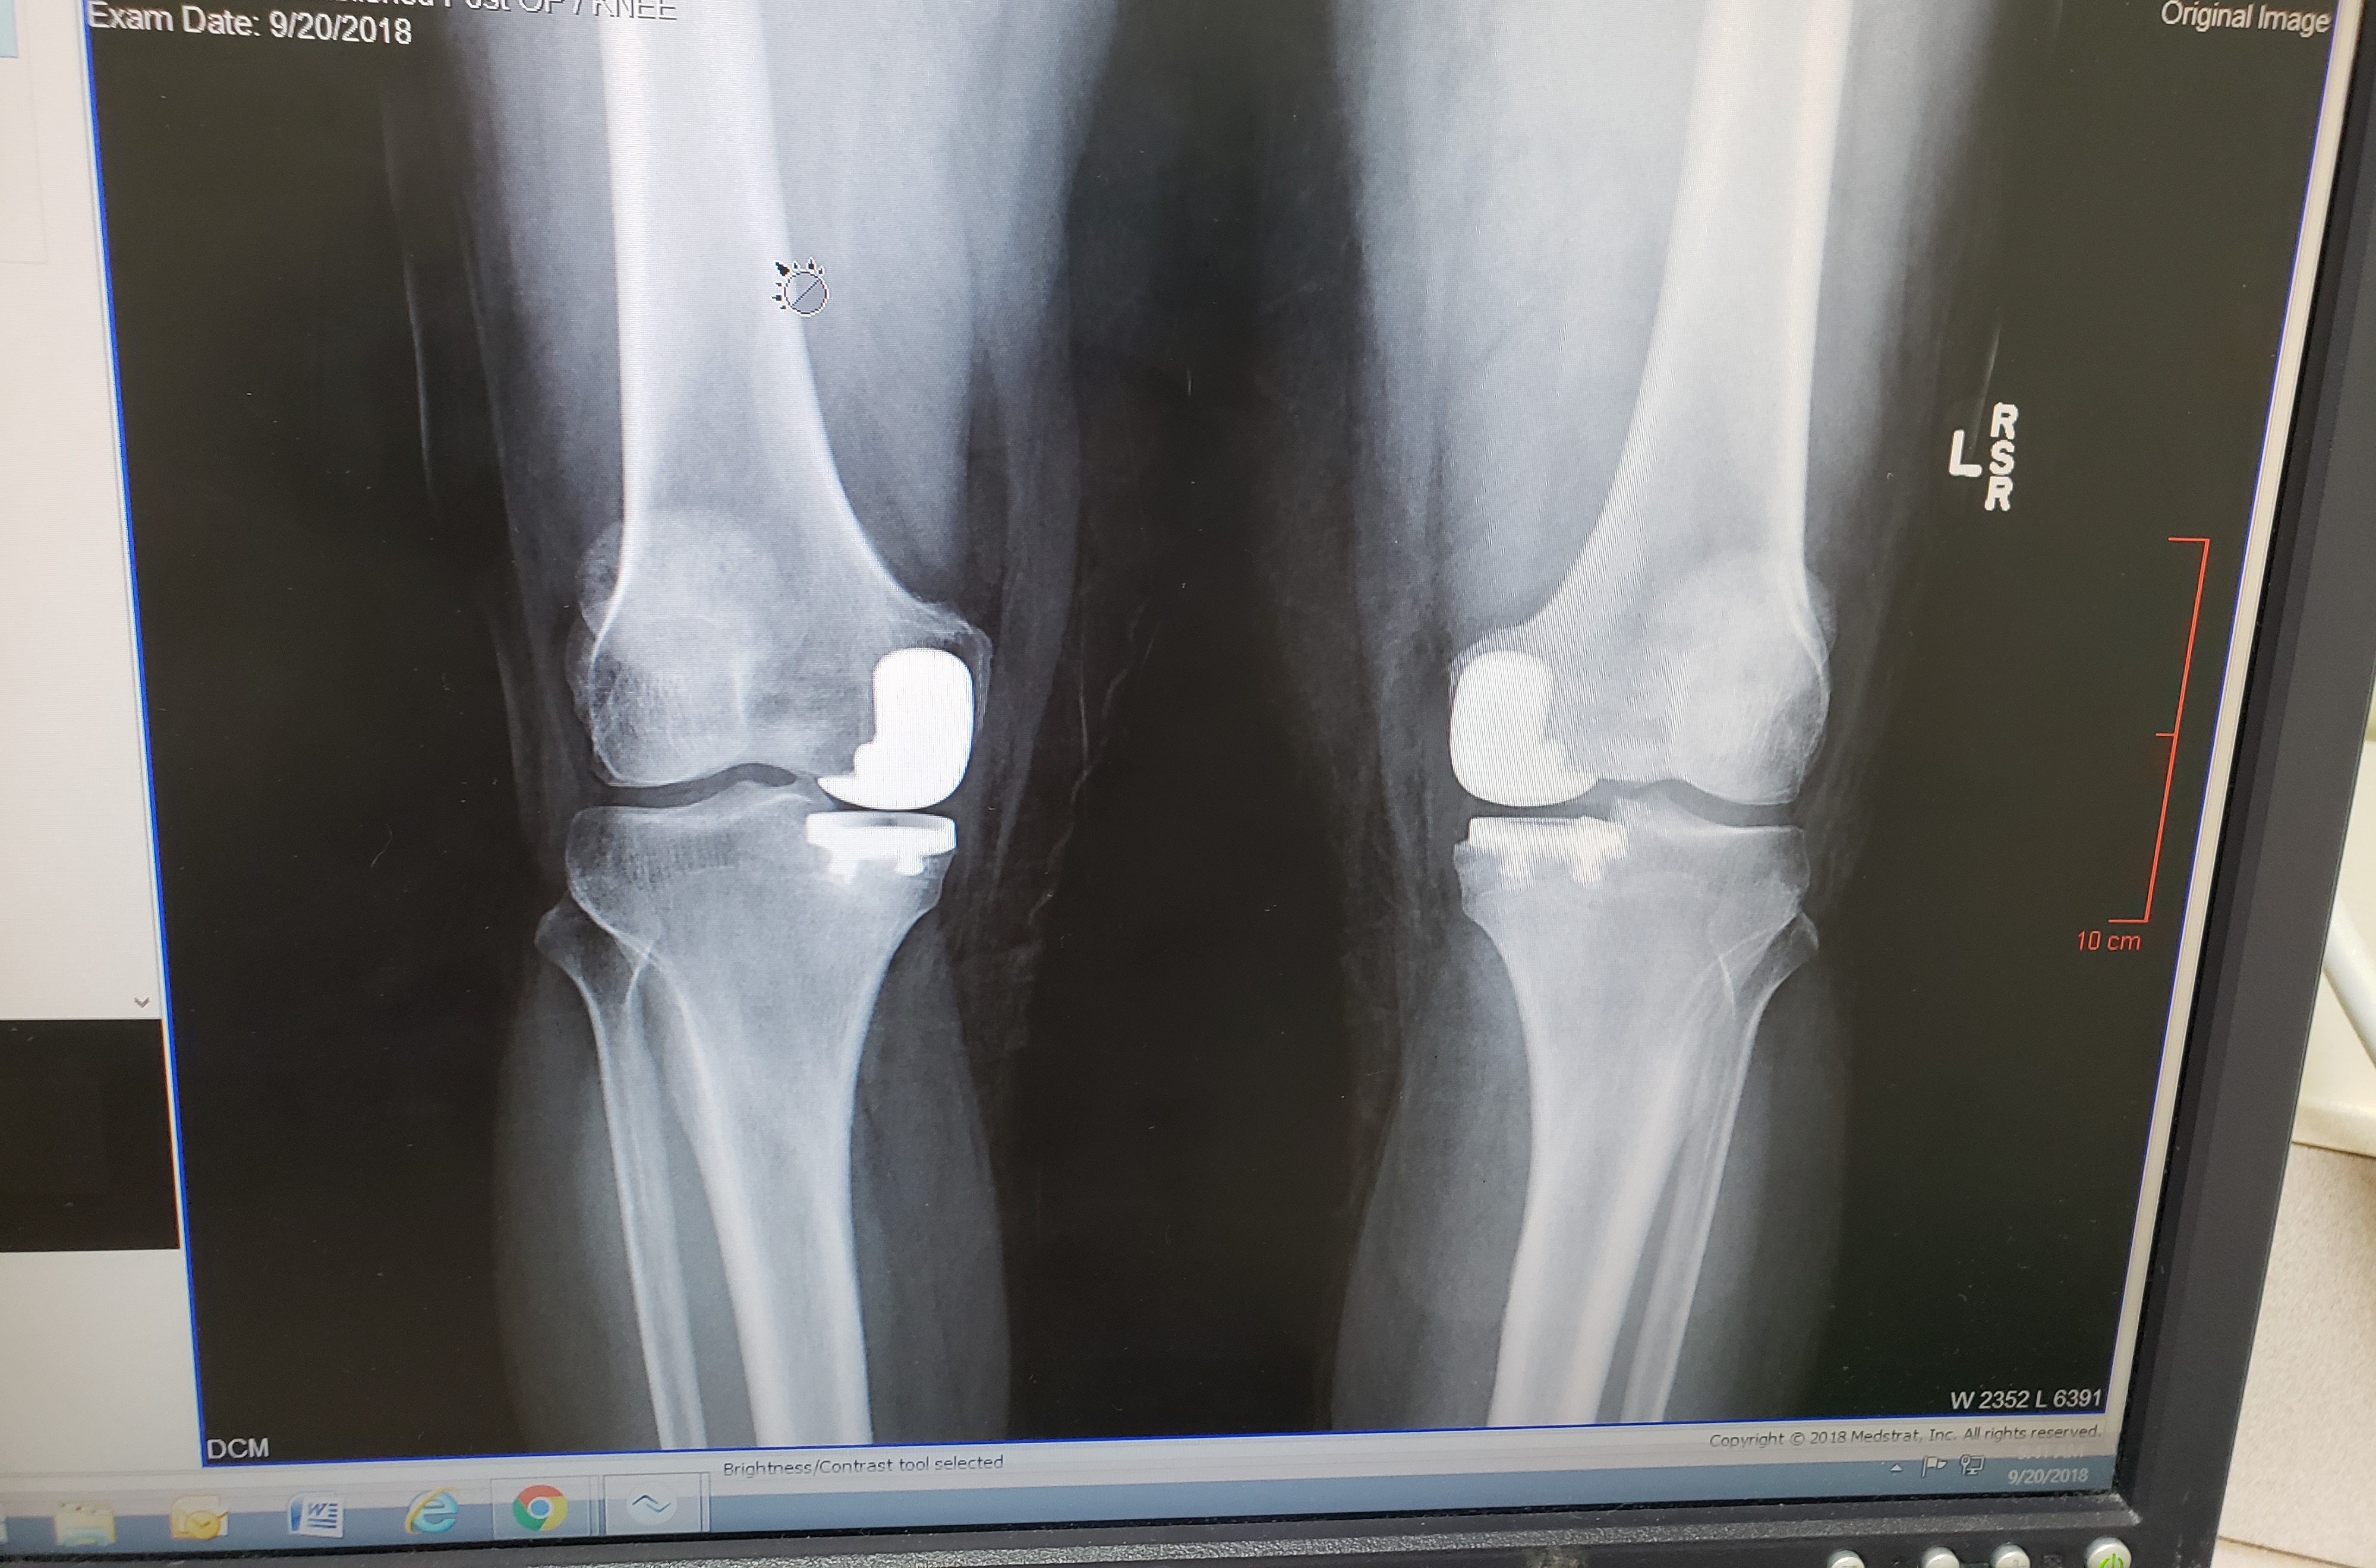

Close Quarters has had a few changes, since last I wrote. Roy is home full time now. 2018 was a year of 2 partial knee replacements and lots of recuperation. Roy actually had 3 surgeries. The first was in March to clean up the cartilage he tore in his left knee right after we got home from camping. He was still in pain, so we opted for a partial knee replacement which happened in June. Since he was relying on his right knee which was actually in worse condition then his left and had begun to hurt, we had them do a partial on it in September. It has been a full year since this all started. We have spent more time in the car back and forth to the doctor and physical therapy. We did it so often, I swear I could drive that road half asleep and miss all the pot holes. It was so nice when he could finally drive. I love to drive but I prefer to do it alone, with the music up loud and singing away.